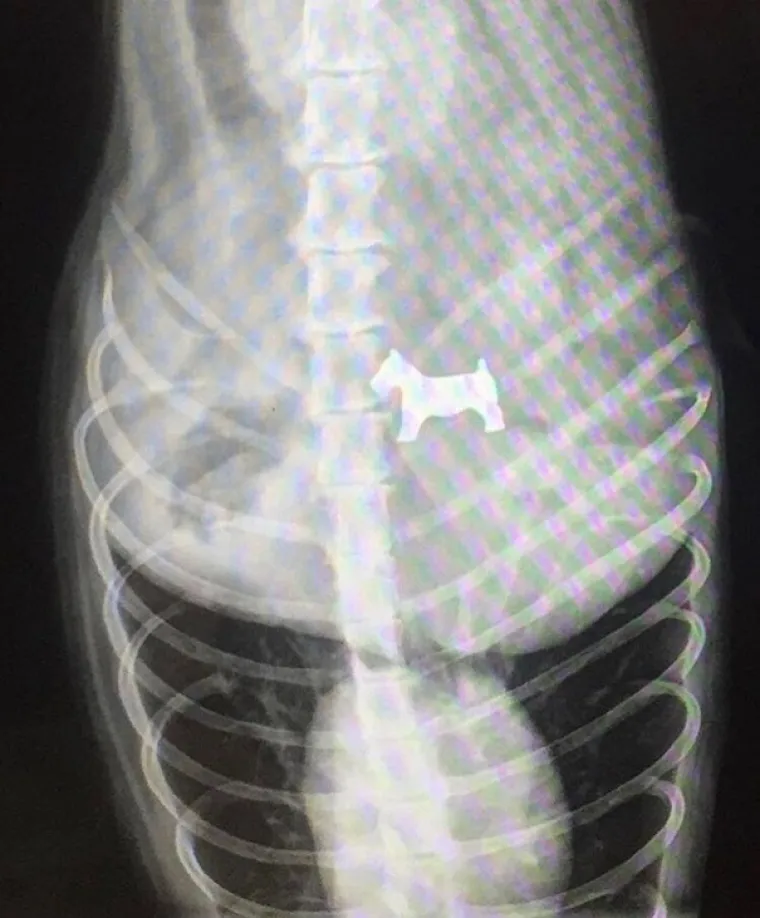

Rengenska snimka psa - koji je pojeo figuricu za monopoly